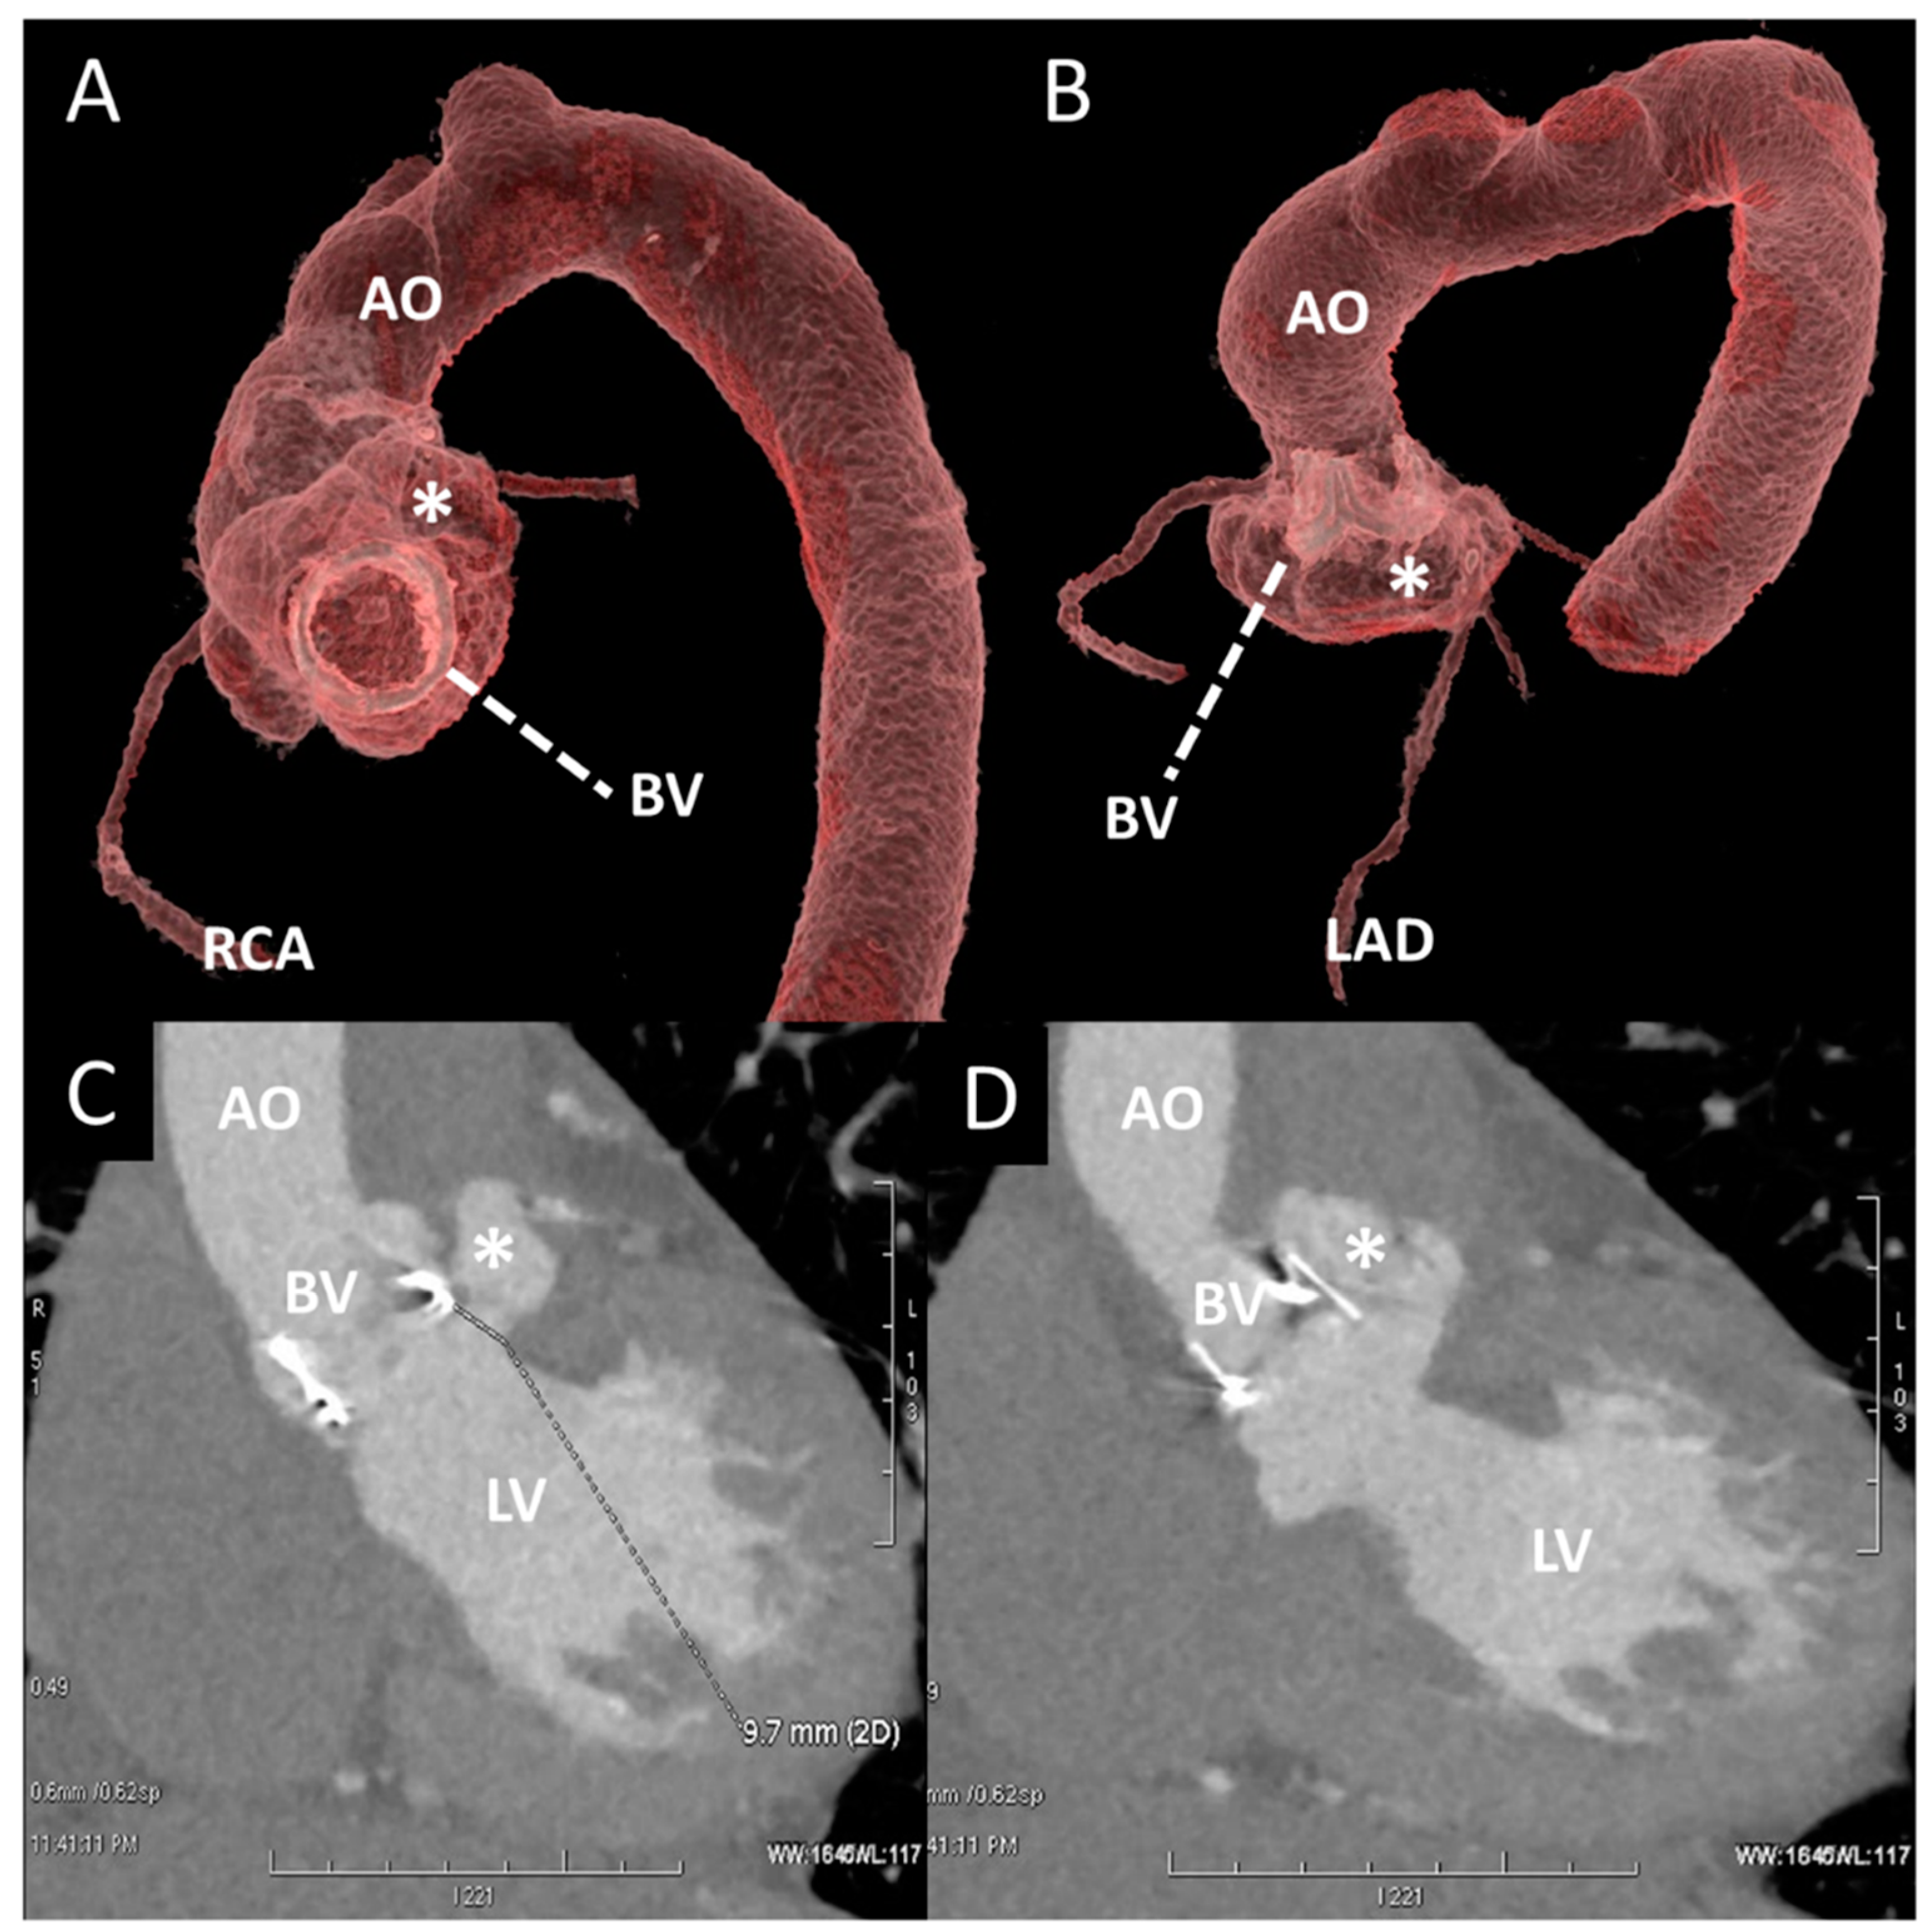

Figure 8. Contrast CT of a pseudoaneurysm (post endocarditis) of aortic root in a patient with aortic BV. (A,B) A 3D reconstruction of aortic root and thoracic aorta (AO). The asterisk shows the pseudoaneurysm adjacent to the left coronary sinus and the origin of left LAD. (C,D) Oblique planes of BV and aortic root: in (C), the white line shows the entrance of the pseudoaneurysm (*) right below the BV. BV, bioprosttic valve; LAD, left anterior descending artery; LV, left ventricle; RCA, right coronary artery.